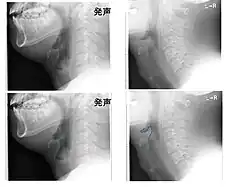

Left column: Normal epiglottis. Right column: Epiglottitis. -

On lateral C-spine X-ray, the thumbprint sign describes a swollen, enlarged epiglottis.[11] A normal X-ray, however does not exclude the diagnosis.[11] An ultrasound may be helpful if specific changes are present, but its use as of 2018 is in the early stages of study.[11]